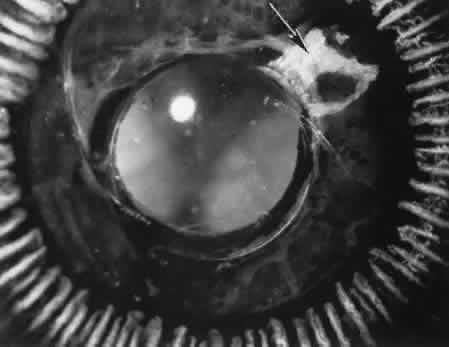

Cyclocryotherapy, cyclodiathermy (Fig. 20), and therapeutic ultrasonography apply energy directly to the pars plicata and cause lysis of the ciliary muscle and occlusion of the vascular supply, leading to extensive necrosis and scarring. Pressure lowering is accomplished by a reduction of aqueous production. Heat applied to the sclera may cause necrosis and localized scleral thinning. Cold applied to the sclera, unless extreme, does not cause any clinical or histologic changes.

Fig. 20. Cyclodiathermy treatment of the ciliary body to control glaucoma. A. Gross photograph illustrates extensive areas of depigmentation mainly in the region of the pars plana (arrows) rather than the pars plicata. B. Light micrograph of the region of the pars plana illustrates an extensive area of tissue degeneration of the pars plana (between arrows) in the late postoperative course. C. Light micrograph of the destructive effects of cyclocryotherapy also in the region of the pars plana and pars plicata. The ciliary epithelium in the early postoperative period is necrotic and cystic. (Hematoxin-eosin stain; A, × 8; B, × 16.)